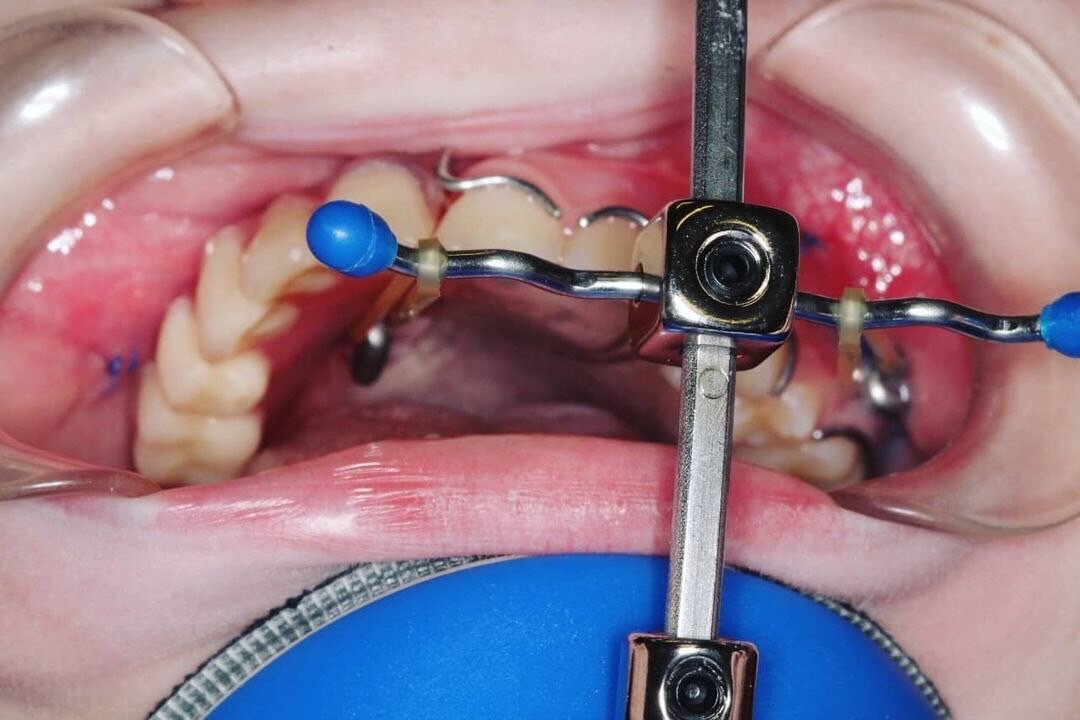

В последствии это приведёт к деформации лица. Поэтому наша задача и цель - попытаться стимулировать рост верхней челюсти. Для этого на верхнюю челюсть установили титановые имплантаты. К ним крепится внеротовая тяга (маска). Эту маску ребёнок одевает на ночь и днём пока находится дома. В среднем 14-18 часов.

Что бы можно было использовать эту конструкцию одновременно со съёмными протезами в съёмных протезах сделали специальные отверстия.